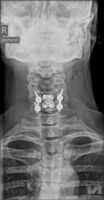

Am Montag, 19.02.2018, begann die Operation um 10 Uhr am Vormittag und dauerte 3,5 Stunden. „Der Patient wies nach seinem fatalen Sturz ein so genanntes Hyperflexionstrauma (Stauchungstrauma) durch die Verletzung des 5. Halswirbels auf. Dieses Trauma war die Ursache für eine gefährliche Instabilität zwischen dem 5. und 6. Halswirbel. Gefährlich deshalb, weil durch ein mögliches Abrutschen der Wirbelkörper 5 und 6 gegeneinander eine schwerwiegende Verletzung des Rückenmarks entstehen kann. Eine operative Stabilisierung der Halswirbelsäule von vorne und von hinten war notwendig (Ventral- und Dorsalstabilisation)“, beschreibt OA Dr. Meusburger. Im Detail heißt dies, dass der Operateur zuerst einen Eingriff von vorne auf die Halswirbelsäule vorgenommen hatte. Die betroffenen Wirbel wurden mit Platte und einem Beckenspan, also einem Knochen aus dem eigenen Becken, der während der Operation entnommen worden ist, stabilisiert.

In der Folge war schließlich noch eine zusätzliche Stabilisierung mit Metallstäben und Schrauben (Implantaten) von der Hinterseite zur vollständigen Konsolidierung notwendig.